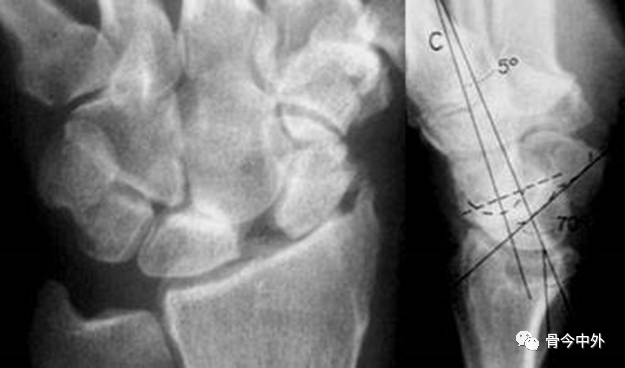

图1 成人期腕关节正侧位及舟骨蝶位片。1.舟骨;2.月骨;3.三角骨;4.豆状骨;5.大多角骨;6.小多角骨;7.头状骨;8.钩骨;9.桡骨茎突;10.尺骨茎突;11.第一掌骨基部。

图2 成人期腕关节正侧位及舟骨蝶位片。1.舟骨;2.月骨;3.三角骨;4.豆状骨;5.大多角骨;6.小多角骨;7.头状骨;8.钩骨;9.桡骨茎突;10.尺骨茎突;11.第一掌骨基部。

图3 成人期腕关节正侧位及舟骨蝶位片。12.舟骨结节。黑色箭头:舟骨腰部;白色箭头:舟骨滋养血管影。

二、测量方法

图4 a.桡骨纵轴线;b.桡骨纵轴线垂线;c.桡骨远端关节面切线;d.尺骨远端关节面水平线。A.桡骨内倾角;B.桡骨茎突长度;C.尺骨茎突长度 。

A.正常为15~35˚ 。若此角度改变,提示桡骨远端骨折或腕关节脱位。

B.正常为8~18mm,且桡骨茎突较尺骨茎突低1~1.5cm。若此长度改变,提示桡骨远端骨折。C.正常为2~8mm。若此长度改变,提示尺骨茎突骨折或尺骨茎突过长(尺骨茎突撞击综合症)